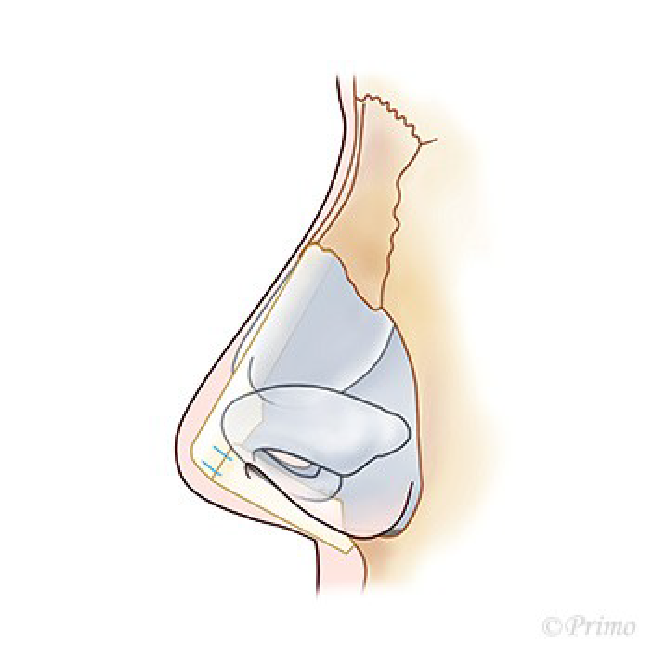

鼻中隔延長術を行った後、感染や何らかの原因で強い炎症を伴って鼻先が拘縮してしまった場合、時期を待って肋軟骨移植による修正を行う方法があります。

拘縮し鼻先や鼻尖が後退している状態の改善を図るため、open approachから拘縮をできるだけ解除します。

肋軟骨で作成したL型フレームを移植します。

肋軟骨L型フレームを外側鼻軟骨と前鼻棘に縫合固定します。

鼻翼軟骨をL型フレームに引き上げ固定します。

必要に応じて鼻柱部分に軟骨移植を追加します。

鼻先を耳介軟骨や軟部組織でカバーします。